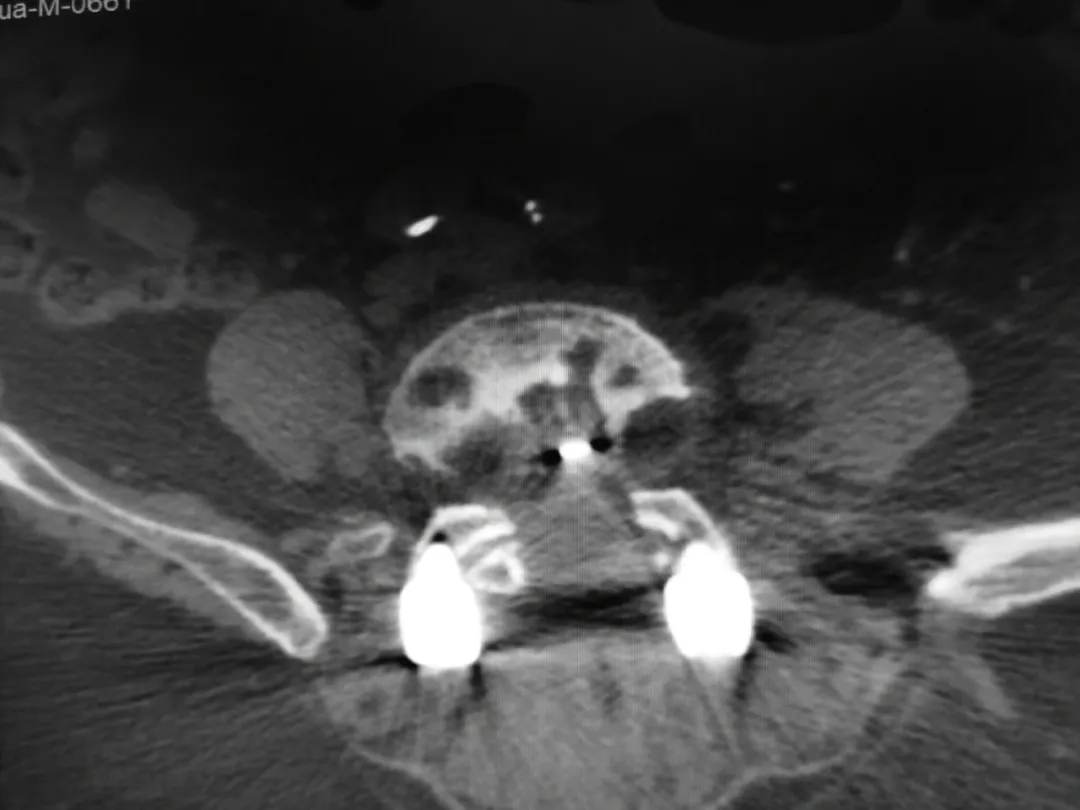

腰椎内固定术后影像:CT可见椎体多个低密度灶。

▲CT